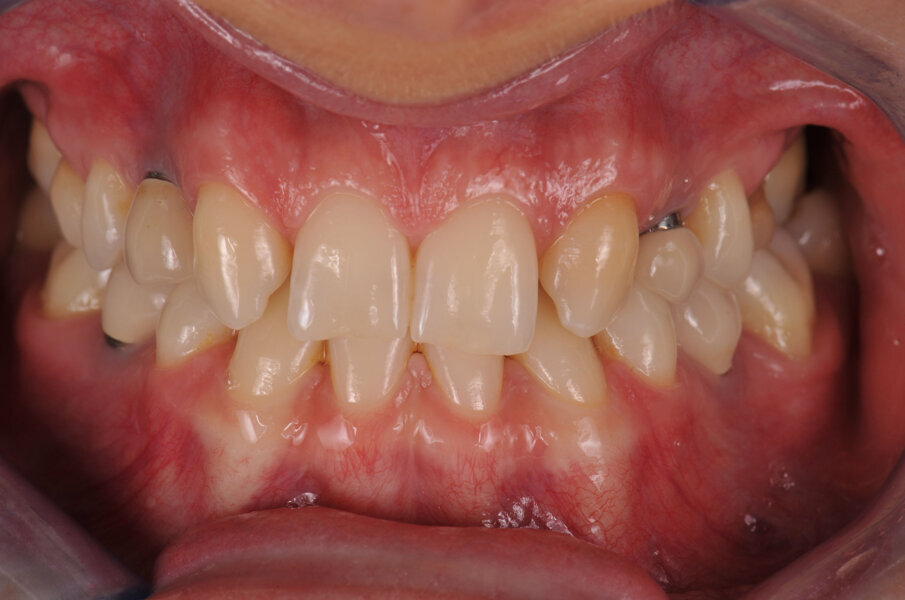

In deze casus is indertijd voor tissue level-implantaten gekozen en na ongeveer achttien jaar in functie is de esthetiek, mede door de vorm van de cuspidaten en het zichtbaar worden van de implantaten, discutabel te noemen (afbeelding 1 en 2).